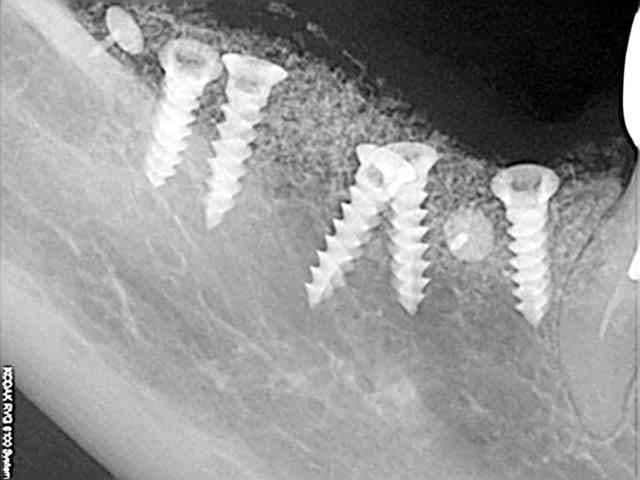

Comme dans la radio de contrôle 1 que tu viens d'envoyer.( qui apparemment est une radio faite juste après ton intervention)

je me dis aussi, à la vu des coupes, que tu repères le V3 trop haut?

dommage qu'on ne les voit qu'en petit.

J'ai parfois des problèmes pour repérer le V3 sur des coupes de conebeam (Vatech, que je fais faire à un copain). Ma pano m'aide pour mieux le repérer (Kodak). Tu n'aurais pas de "vrai" pano pour comparer?